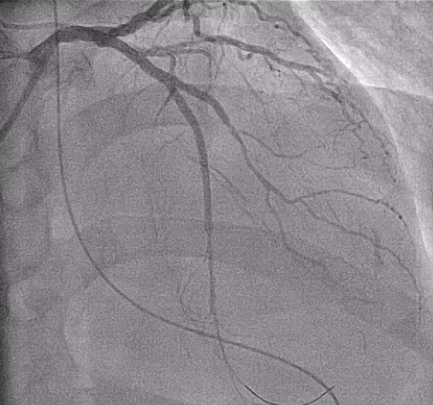

The left main was patent. The LCX had a diffuse long lesion with up to 95% stenosis. The LAD showed a proximal CTO with a blunt stump and well-developed collaterals supplying the distal vessel, giving TIMI 2 flow. The RCA demonstrated TIMI 1 flow with distal critical stenosis, haziness suggesting thrombus, and poor collaterals, identifying it as the culprit for ST elevation and shock.

Inrefractory VT/VF arrest and cardiogenic shock, emergent culprit RCA PCI wasperformed under VA-ECMO and IABP. A Conquest Pro 12 GW crossed the distal RCACTO after failed attempts with Fielder FC and Gaia 2nd. Sequential POBA wasdone, followed by three BMS from RCA-M to RCA-PL, achieving TIMI 3 flow. Abrief attempt to wire LAD-P CTO with a Fielder XT-R failed, suggesting achronic occlusion, and the procedure was stopped due to instability. Afterneurological recovery, staged LAD CTO PCI was performed. Angiography confirmedLAD-P CTO with a blunt stump, severe LCX disease, and patent RCA stents.Antegrade wiring was initiated with an XB 3.5/7Fr GC. A Gaia 2nd entered aseptal branch using a Trek 1.2¡¿6 mm OTW BC. With APT 1.9Fr and Sasuke MCs,multiple GWs (XT-A, UB3, Conquest Pro 12) attempted proximal cap penetrationbut tracked into false lumens. IVUS from septal and D1 branches was used forcap clarification but remained inconclusive. Usingan IVUS-guided parallel-wire approach, a Progress 200T achieved true–false–truecrossing into distal LAD. Sequential 1.0–2.5 mm BC dilatation prepared thevessel. Given a Medina 1,1,1 LAD–D1 bifurcation, a DK-Crush technique waschosen. A Synergy 2.5¡¿48 mm DES was deployed from LAD-M to LAD-D, crushed,rewired, and optimized. A second 2.5¡¿48 mm DES was placed from LAD-P to D1,followed by kissing balloons and final POT. Final angiography showed TIMI 3flow with good expansion.